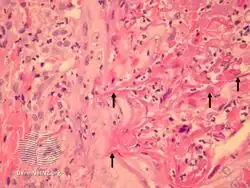

Perforating folliculitis is a skin condition in humans characterized by discrete follicular keratotic eruptions involving mainly the hairy parts of the extremities.[1]: 539–540

- Perforating folliculitis/pathology